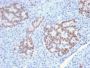

Jurkat cells. Small Intestine or Pancreas.

IHC, FFPE (verified)

IHC (FFPE) (verified)